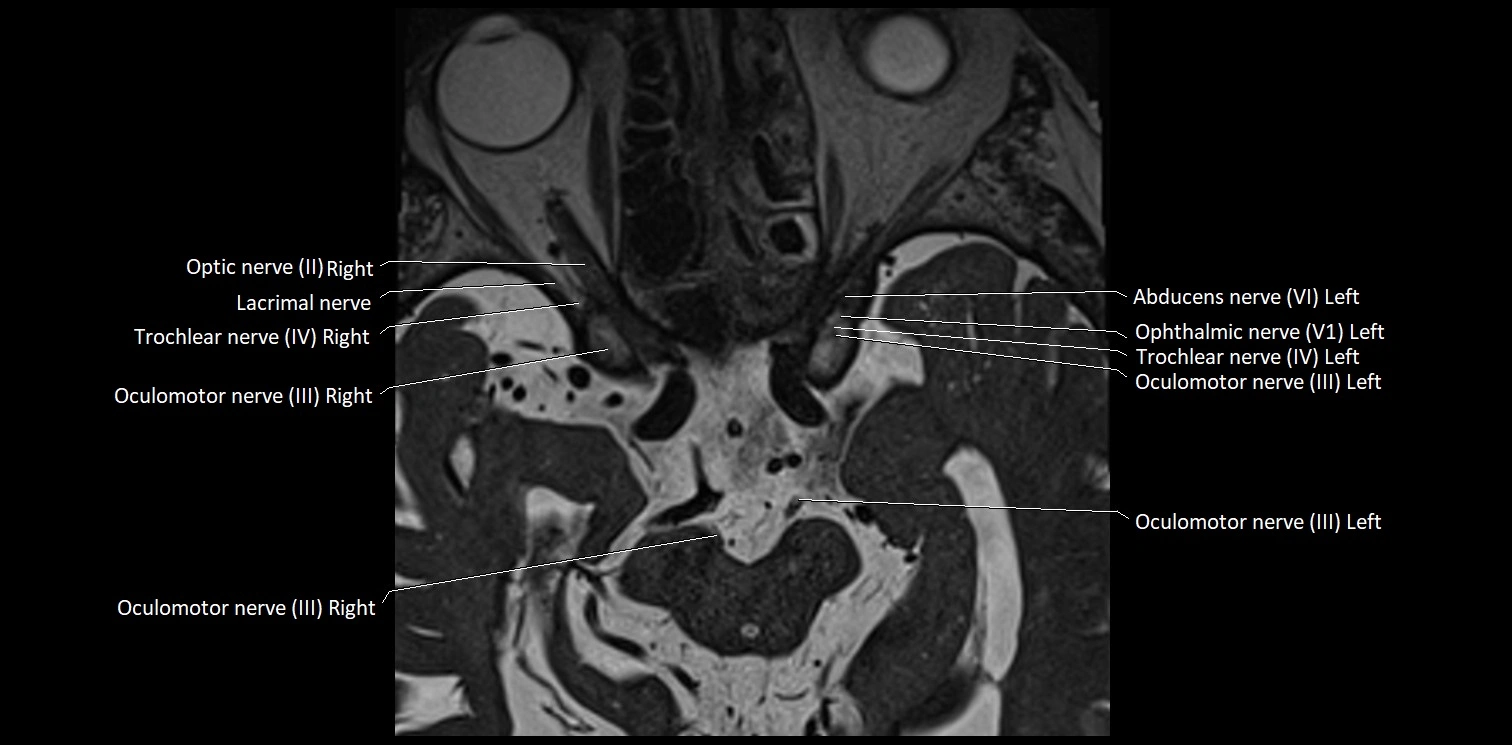

MRI images

image